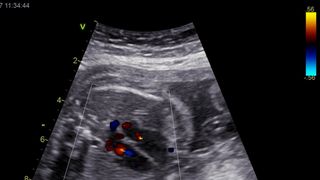

A Ecocardiografia Fetal é uma ecografia (ou seja, uma técnica de imagem que utiliza ultrassons) dirigida ao coração do feto. Utiliza-se um aparelho semelhante aos usados nas ecografias obstétricas normais, mas com algumas técnicas diferentes que permitem, por exemplo, estudar o fluxo do sangue dentro do coração.

Com o Ecocardiograma Fetal o Médico consegue observar o interior do coração do bebé (as quatro cavidades, as válvulas, as paredes do coração) bem como as grandes artérias e as veias que entram no coração. Assim, se houver algum problema grave ele é facilmente detetado.

Não podemos esquecer que a circulação do feto é diferente da circulação após o nascimento (o feto não respira, recebendo o Oxigénio de sua mãe, através do cordão umbilical), pelo que pouco sangue vai para os pulmões e existem curto-circuitos entre os lados direito e esquerdo da circulação, com pressões semelhantes dos dois lados, ao contrário do que se passa após o nascimento em que os curto-circuitos encerram e as pressões ficam diferentes.